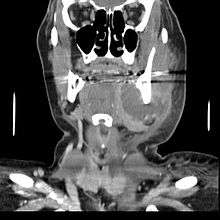

.jpg)

The pain is continuous and may be described as extreme, growing, sharp, shooting, or throbbing. Putting pressure or warmth on the tooth may induce extreme pain. The area may be sensitive to touch and possibly swollen as well. This swelling may be present at either the base of the tooth, the gum, and/or the cheek, and sometimes can be reduced by applying ice packs.

An acute abscess may be painless but still have a swelling present on the gum. It is important to get anything that presents like this checked by a dental professional as it may become chronic later.

In some cases, a tooth abscess may perforate bone and start draining into the surrounding tissues creating local facial swelling. In some cases, the lymph glands in the neck will become swollen and tender in response to the infection. It may even feel like a migraine as the pain can transfer from the infected area. The pain does not normally transfer across the face, only upwards or downwards as the nerves that serve each side of the face are separate.